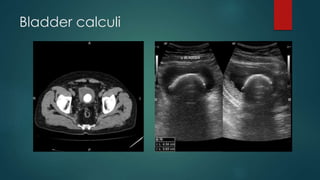

Bladder calculi

 Bladder calculi occur either from migrated renal calculi or urinary

stasis.

Bladder calculi can be divided into primary and secondary stones:

 primary: stones form de novo in the bladder

 secondary: stones are either from renal calculi which have migrated

down into the bladder, or from concretions on foreign material (e.g.

urinary catheters)

associated with :-

 bladder outlet obstruction

 cystocoele

 neurogenic bladder

 foreign body.

Radiographic features

 Plain Film

 Usually densely radio-opaque, calculi may be single or multiple and often large.

Frequently lamination is observed internally, like the skin of an onion.

 Ultrasound

 Sonographically they are mobile, echogenic, and shadow distally.

 They may be associated with bladder wall thickening due to inflammation.